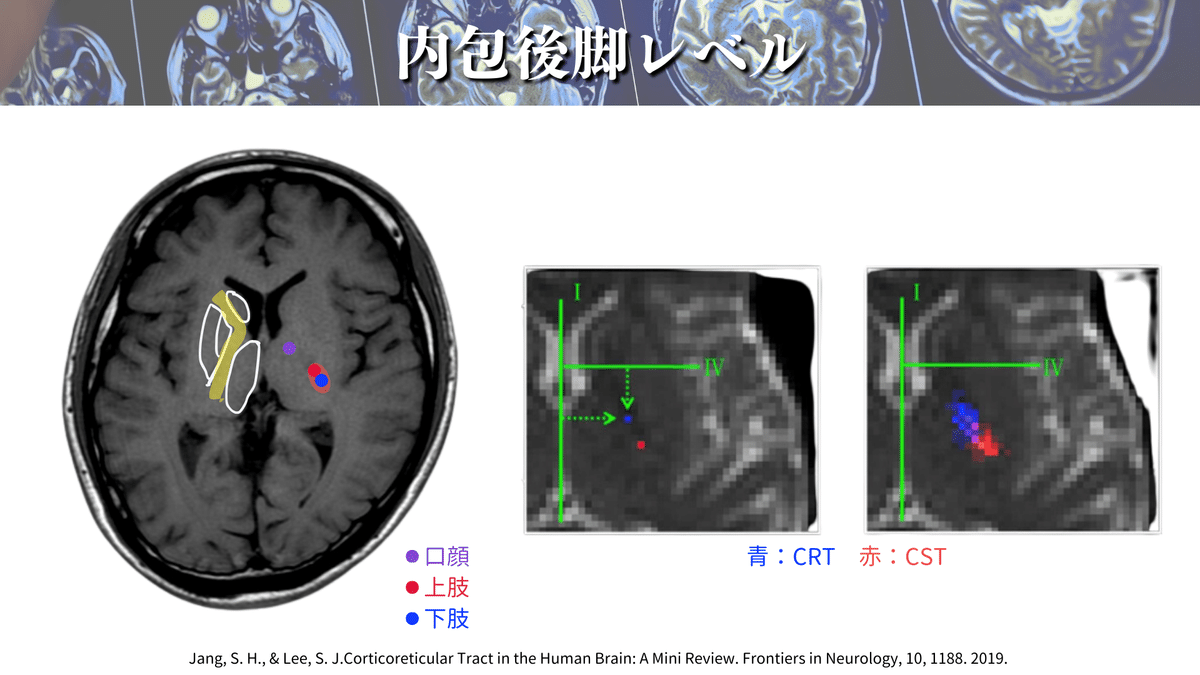

もっとわかりやすく見てみると〜👁️✨

こんな風になります😆

赤く染めた部分がCST(上下肢・体幹)の通過位置になります👍

口顔の部分の運動線維の皮質延髄路は、内包膝を通って下降していきます👄

つまり、内包後脚部分を通るのは上下肢・体幹のCSTになるということですね✋🦶